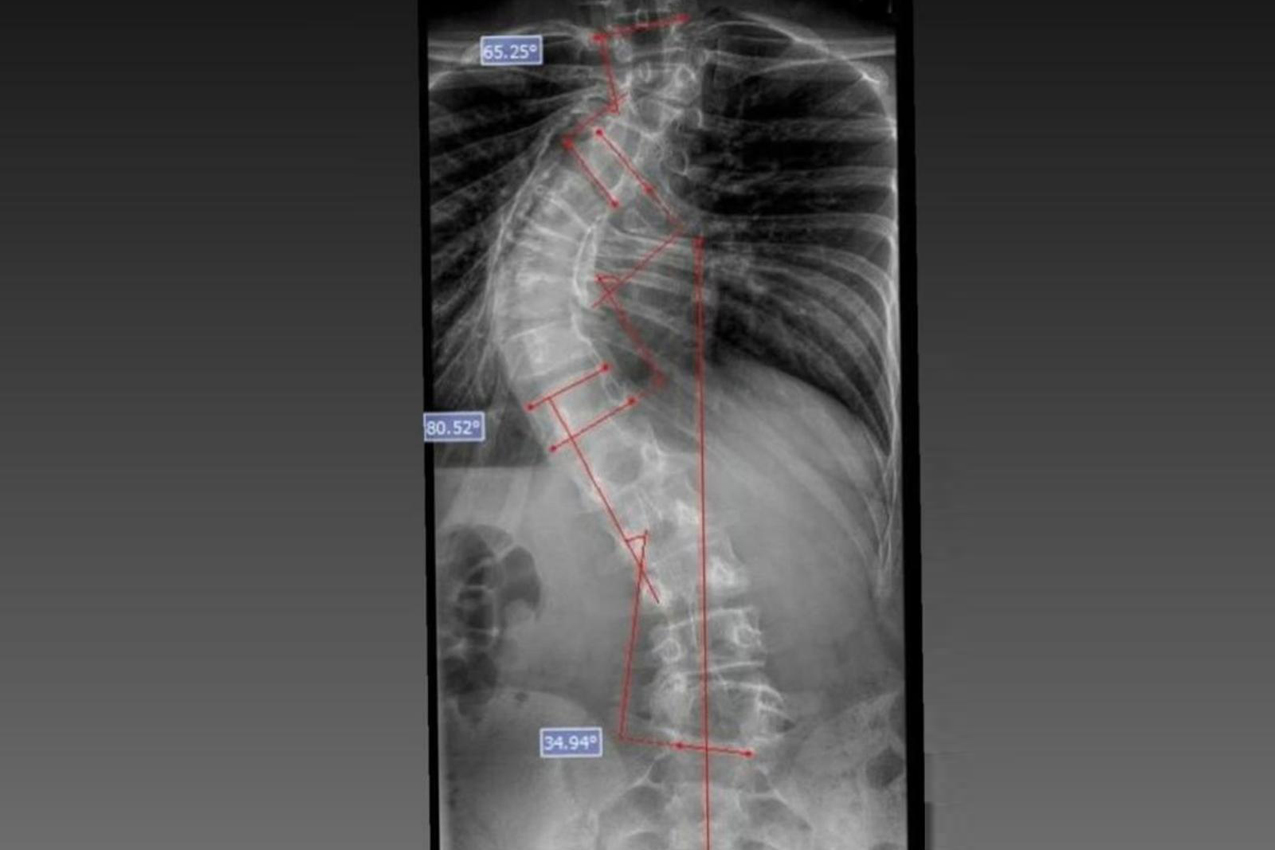

Aos 13 anos, Laura Dzwielewski Menegaz sonhava em voltar a montar a cavalo sem sentir dor. Diagnosticada com escoliose, ela passou por uma cirurgia de correção da coluna no Complexo Hospitalar do Trabalhador, em Curitiba. Antes do procedimento, atividades cotidianas eram acompanhadas por dores constantes e limitações físicas.

Casos como o dela são atendidos pelo Departamento de Deformidades Pediátricas da Coluna Vertebral, implantado em 2023, que se tornou referência no tratamento de escoliose em crianças e adolescentes. Desde então, mais de 200 cirurgias foram realizadas, além de tratamentos conservadores, como fisioterapia e uso de coletes ortopédicos.

A escoliose é um desvio lateral da coluna vertebral que pode ter diferentes causas e, de acordo com especialistas, o diagnóstico precoce é fundamental para evitar a progressão da curvatura e reduzir a necessidade de procedimentos mais complexos.